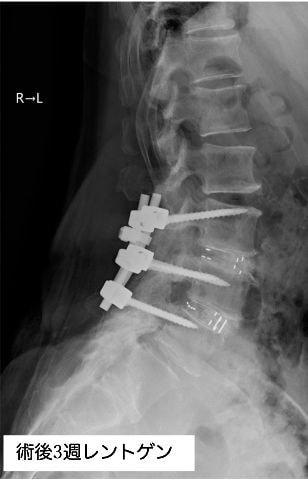

手術の2年ほど前から腰から両殿部痛、下肢後面のしびれが出現し、他院にて腰部脊柱管狭窄症の診断を受けました。徐々に症状は増悪し、手術前は間欠性跛行(※)で長距離の歩行が困難となり、家事を行う際も何度も休憩が必要な状態でした。また、痛みを避けようとするためにかばった姿勢(写真1)となり、筋力低下・可動域制限を認めている部分がありました。その後、手術希望にて当院を受診され、腰椎後方除圧椎体固定術(cortical Bone Trajectory:CBT)が行われました。

術前にあった痛み・しびれは術後2週目にはほぼ消失し、廊下歩行なども積極的に行えるようになりました。術後3週目には屋外歩行を行い、約20分程度の散歩が可能となり、間欠性跛行の改善も得られました。姿勢の改善もみられてました。(写真2)

腰椎後方除圧椎体固定術(CBT)を行った方の入院期間は、術前術後合わせて約4週間です。術前のリハビリと、術後は全身状態を確認しながら、主に体幹・下肢機能、歩行能力の強化、パンフレットを使用して腰椎に負担の少ない姿勢・動作の指導などを行います。